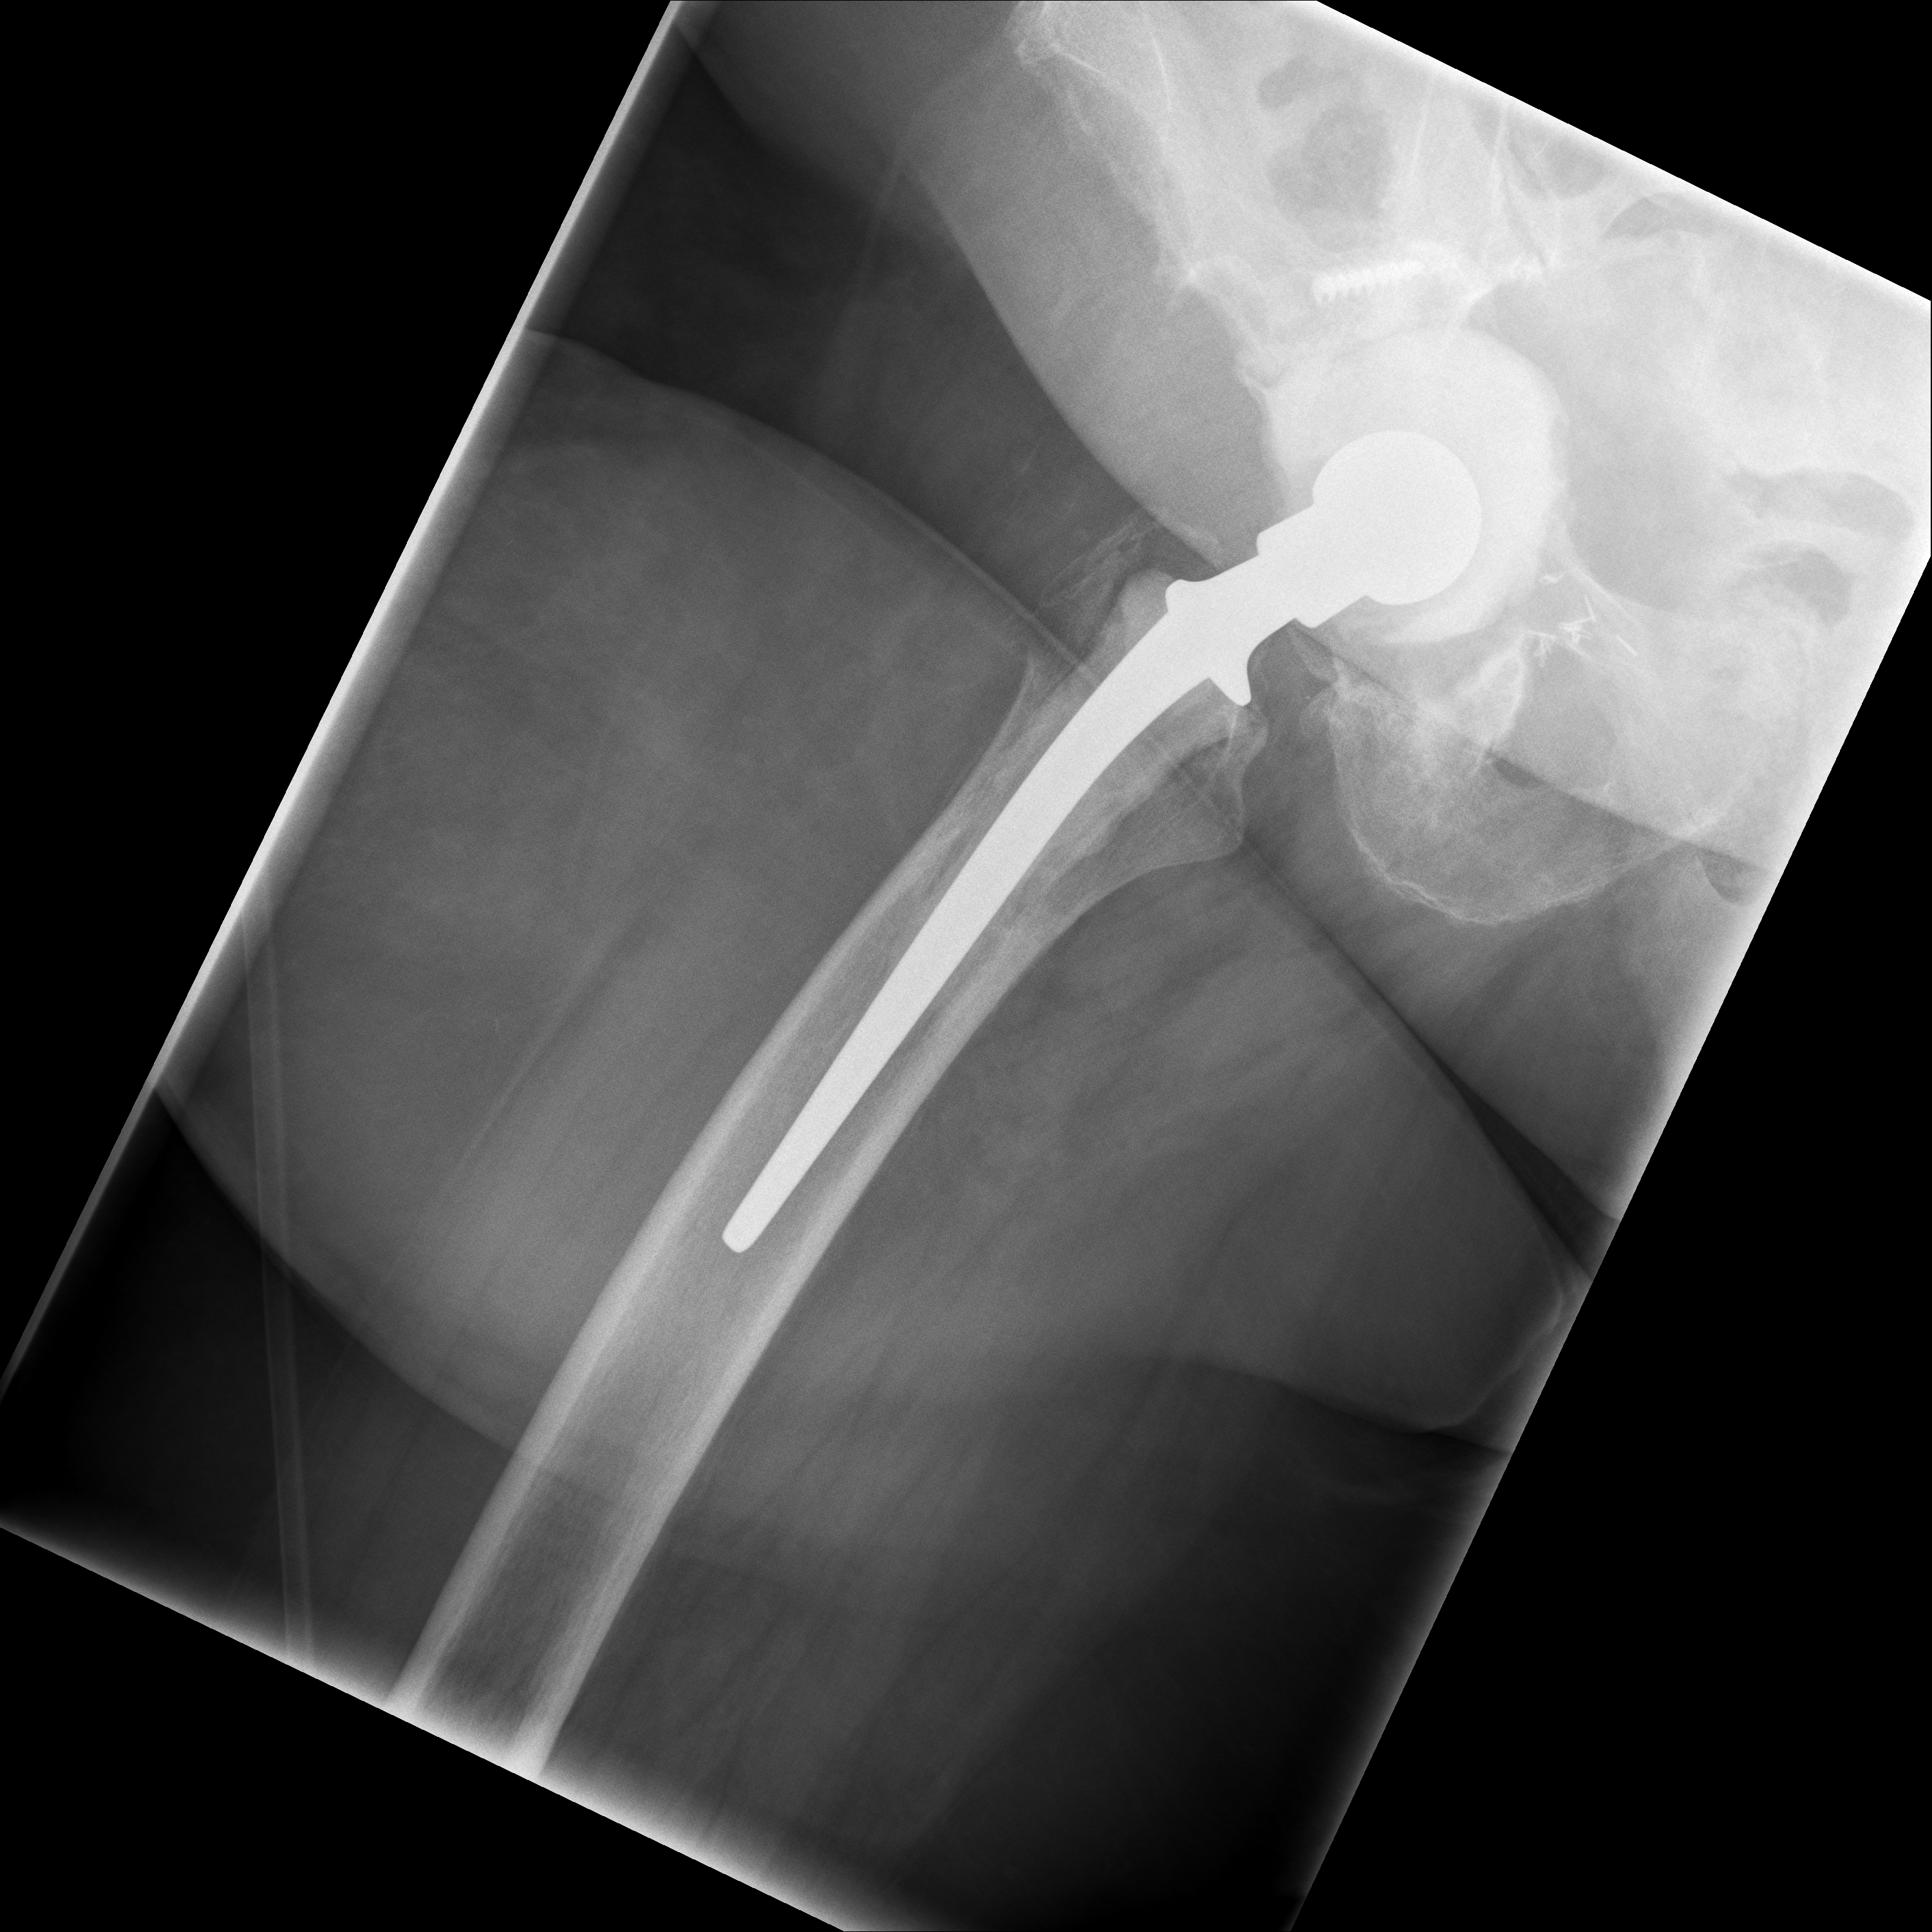

24.02.2026 - Neue TEP

Röntgen Februar 2026

Neue Hüft-TEP rechts nach Wiedereinbau

24.02.2026 - Neue TEP!

Becken 2026

Verlauf: Die Luxation/Pfannendislokation führte zur stationären Aufnahme im Universitätsklinikum Heidelberg (28.12.2025). Am 30.12.2025 wurde die TEP entfernt und ein Spacer implantiert. Infektnachweis: Enterococcus faecalis. Am 19.02.2026 wurde die neue Prothese erfolgreich eingebaut (stationär bis 05.03.2026). Komplikationsloser Verlauf, regelrechte Implantatlage im Röntgen. Entlassung mit 20kg Teillast, Amoxicillin für 6 Wochen. Wiedervorstellung am 09.04.2026.

24.02.2026 - Postoperativ

Röntgen Becken + Hüfte rechts (Kontrolle nach Wiedereinbau)

3 Aufnahmen | Becken tief + 2x Hüfte Lauenstein | 5 Tage nach OP

24. Februar 2026

Postoperative Röntgenkontrolle

Röntgen Becken tief + 2x Hüfte Lauenstein R – Kontrolle 5 Tage nach Wiedereinbau.